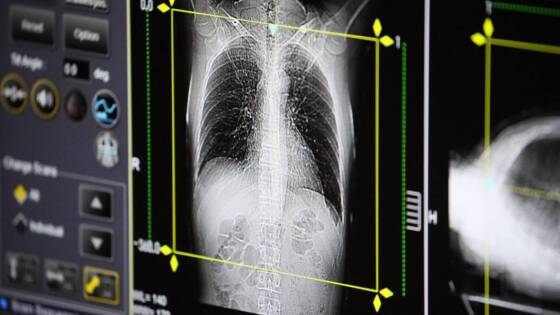

Врач назвала признаки развития пневмонии

Врач-терапевт Ирина Ярцева рассказала, как распознать у себя пневмонию и не допустить развития серьёзных последствий.

Признаками пневмонии являются высокая температура, кашель с мокротой, одышка, боли в грудной клетке при отсутствии насморка и боли в горле, объяснила терапевт «Вечерней Москве».